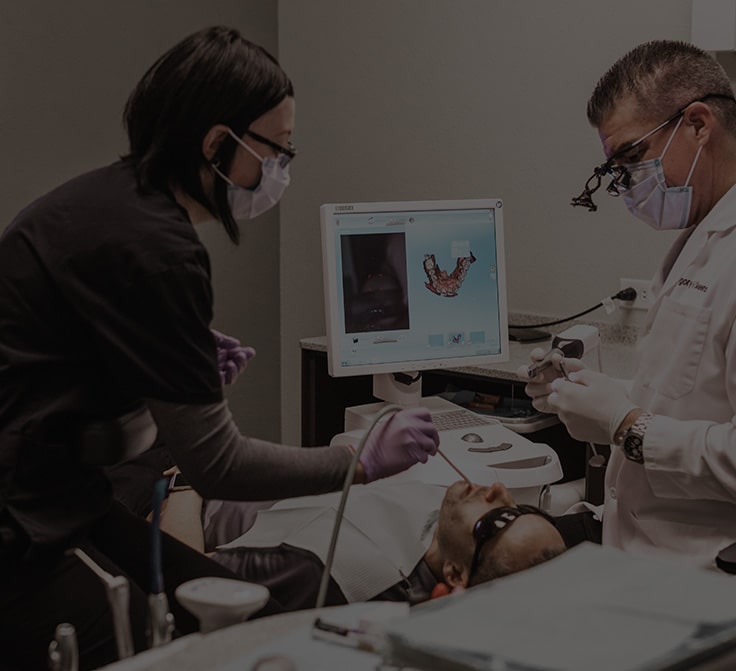

Why CEREC Same Day Crowns May Be Best For You

Sometimes a dental filling just isn’t enough to support a tooth from wearing down or fracturing. In this case, a dental crown is the best solution to help restore a tooth to its natural function and esthetics. At Skeens Family Dentistry, we utilize the most advanced dental techniques like CEREC same day crowns. This level […]

LEARN MORE ABOUT OUR GUIDING PRINCIPLES AT ENCINITAS FAMILY DENTISTRY

At our core, Encinitas Dentistry is a dental practice devoted to restoring and enhancing the natural beauty of your smile. How we accomplish that goal is what makes us stand out. We mingle time-tested approaches to oral care with state-of-the-art technology and procedures to deliver beautiful, long-lasting smiles!